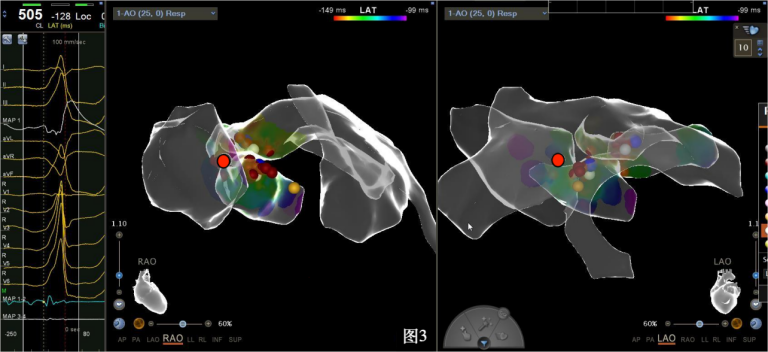

手术中,周明礼团队凭借其丰富的临床经验和精湛的技术,穿刺右股动脉后,将消融大头顺利送入主动脉,于主动脉瓣上标测到最早点(图3红色点)领先体表8ms,电位不理想,果断去到主动脉瓣下左室穹顶部标测,标测到最早点(图4白色点)领先体表25ms,放电消融3s,早搏消失,消融90s后观察2min后,早搏恢复,在该有效点周边补充消融,早搏依旧未能消失,考虑起源点较深,内膜消融未能透壁损伤到起源,随